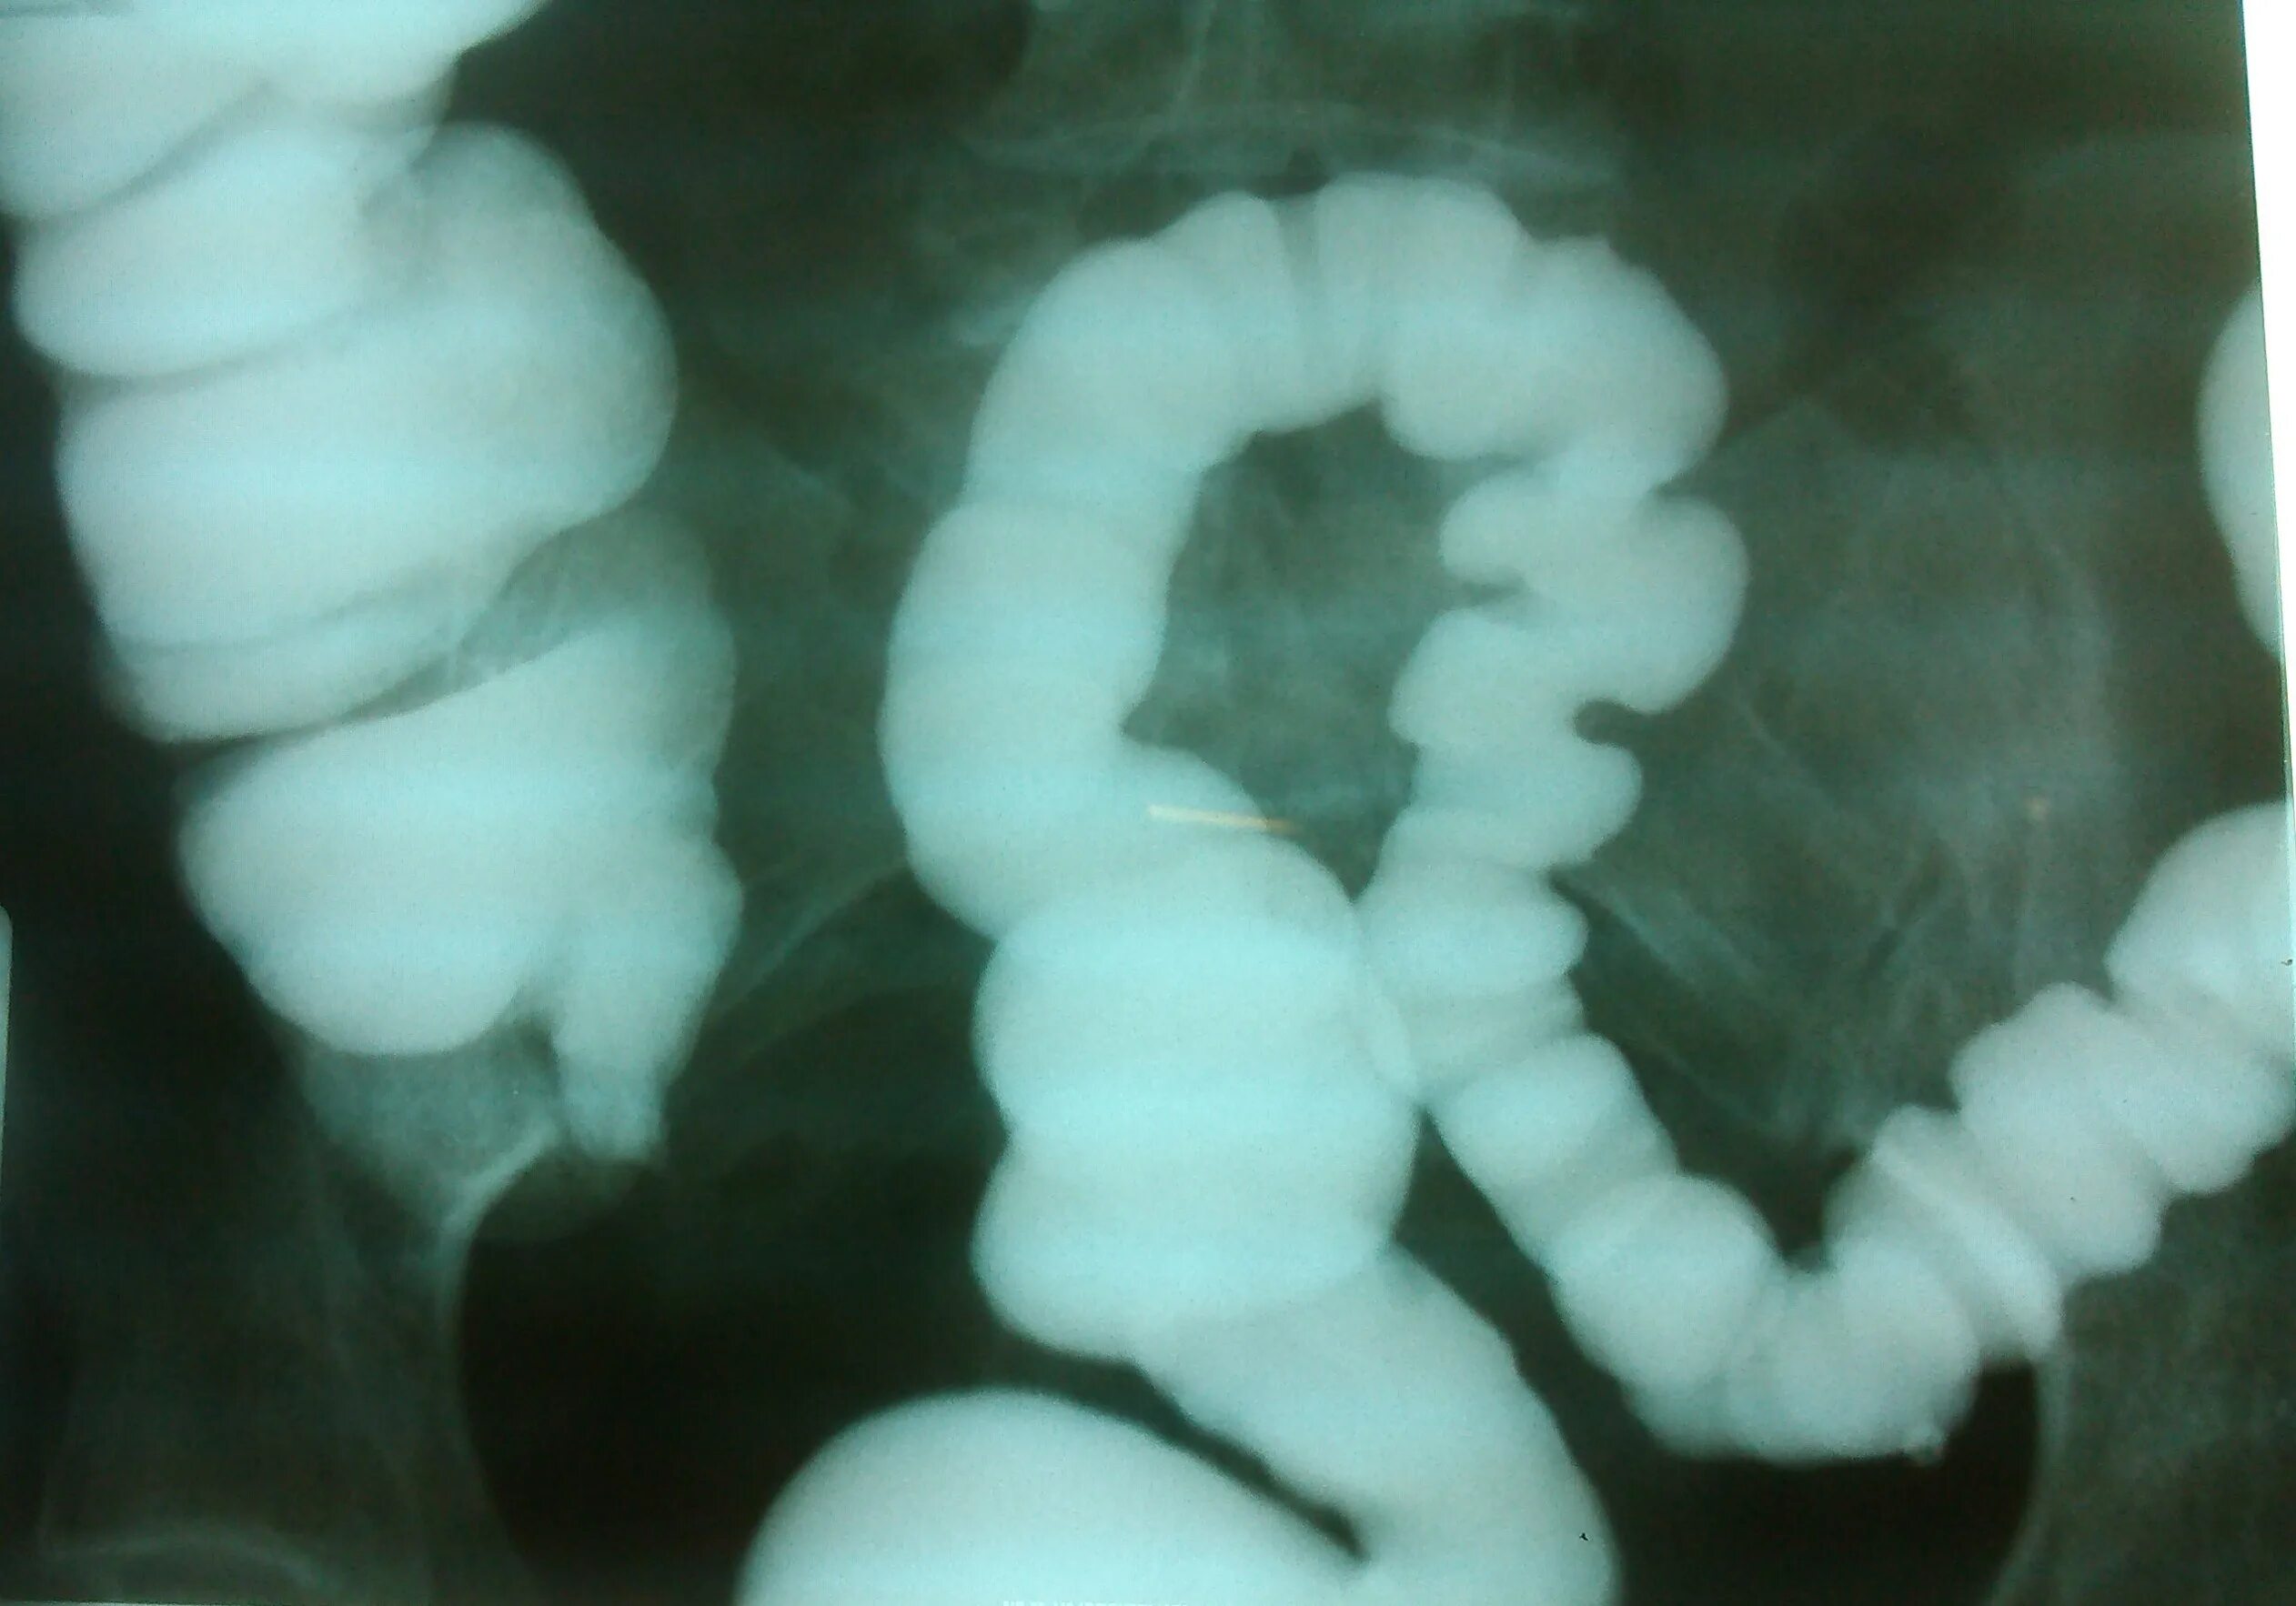

Кишечник после ирригоскопии